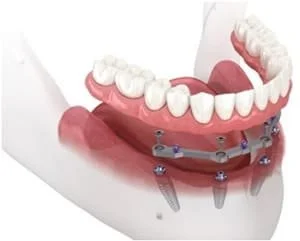

Bar-retained Over-Dentures: The denture is held in place by being attached to a bar which is secured to 2 or more implants. This treatment is very secure and stable.

All-on-4: Whether you are dealing with the headache of loose dentures or are looking for an option to replace your failing natural teeth, All-on-4 implants could be a good option for you.

All-on-4 dental implants also referred to as, teeth-in-a-day, permanently replaced a full arch using 4- 6 precisely placed implants and a dental bridge. The process allows for the total rehabilitation of upper and or lower arches, closely replicating the function of your natural teeth. This is something you simply cannot acquire with a removable denture.